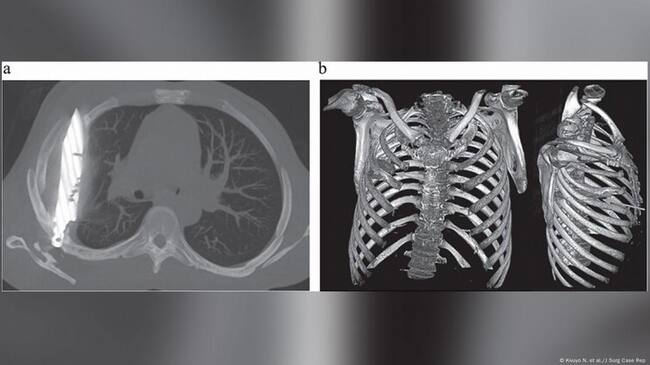

Cuando los médicos examinaron al paciente, observaron que la parte frontal del tórax derecho estaba hundida y que ese lado no se expandía del todo al respirar. Una radiografía reveló la impactante verdad: había “un objeto metálico retenido” dentro de su tórax.

La tomografía computarizada confirmó los detalles: una hoja completa de cuchillo atravesaba su cavidad torácica.

Había entrado por la espalda, cerca de la escápula derecha, deslizándose entre la quinta y sexta costilla, y su punta se encontraba entre la tercera y cuarta costilla del frente. El arma estaba rodeada de pus y tejido necrótico, y las imágenes mostraron fracturas ya curadas en la escápula y varias costillas.